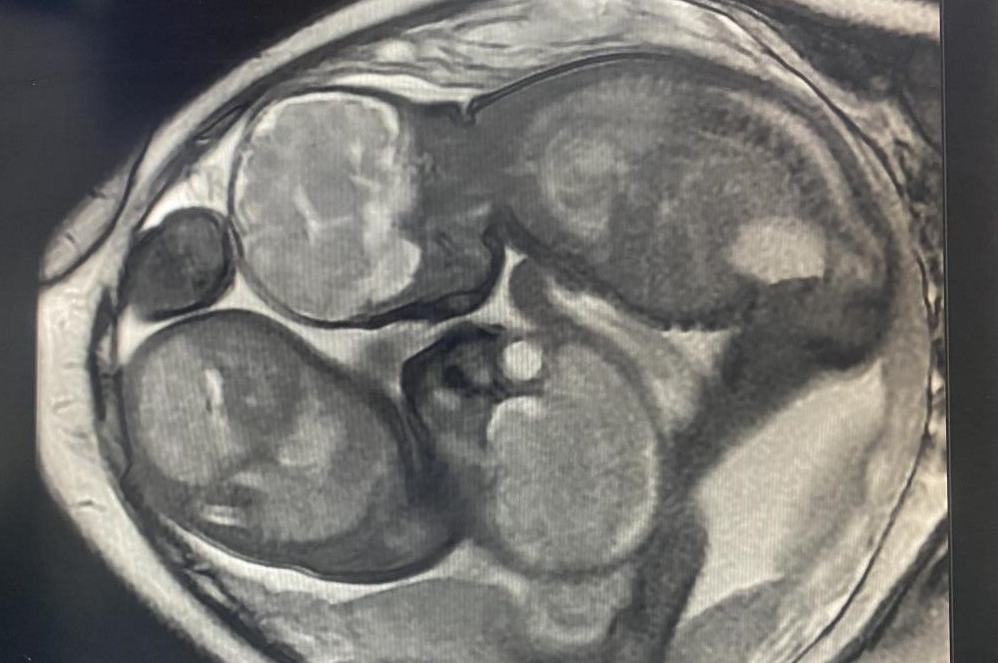

胎儿磁共振检查不存在电离辐射,它的视野大、软组织分辨率高,可以通过任意的切面扫描来显示胎儿的全貌。并且不受母体过度肥胖、羊水过少、多胎、母体子宫肌瘤、胎儿骨骼遮挡、孕晚期胎头入盆等情况的限制,尤其对胎儿颅脑发育评估有无可替代的优势。

1.诊断价值最大的是胎儿中枢神经系统异常:临床常见检查原因如后颅窝池宽,需要MRI来确认是否为Dandy-Walker畸形、Joubert综合征、蛛网膜囊肿、Blake囊肿等;后颅窝显示不清,需要除外ChiariⅡ畸形。其次为侧脑室宽,需要MRI确认是否合并胼胝体发育不全、结节性硬化、脑回发育畸形、脑出血、脑肿瘤、脑积水、积水性无脑、前脑无裂畸形、脑脊膜膨出等。确认超声软指标异常是否合并严重畸形对于妊娠结局至关重要。

5.胎儿腹部结构发育异常:胆总管囊肿;胎儿肾脏发育不良如马蹄肾、异位肾、多囊性发育不良肾(MCDK)、婴儿型多囊肾等;MRI可以明确胎儿肾积水原因及程度,如肾盂输尿管连接处梗阻(UPJO)、输尿管异位开口等,并可以通过特殊序列初步间接提示肾脏功能。